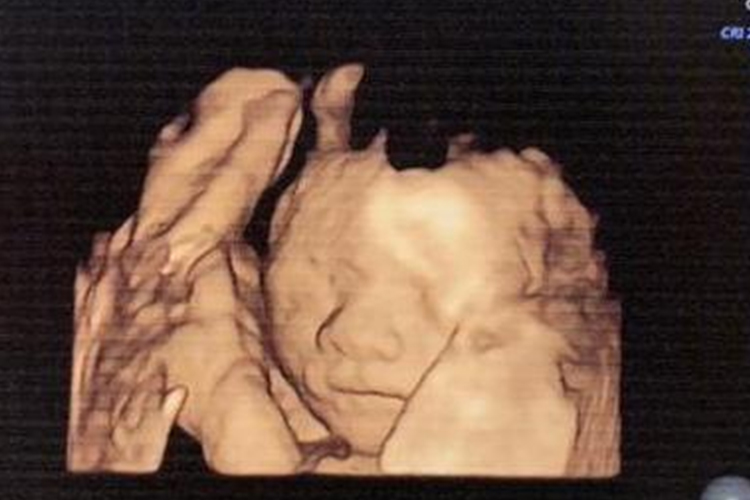

孕二十一周属于妊娠中期,该时期胎儿快速发育,可通过超声检查明确其发育状况。此时胎儿双顶径49-51mm,胎儿身长约为25cm,体重约为320g,临床可听到胎心音。胎儿全身有毳毛,各脏器均已发育,可以看到鼻子、嘴巴、眼睛等,胎儿开始出现吞咽以及排尿功能。同时皮下脂肪开始沉积,但皮肤仍呈皱缩状。